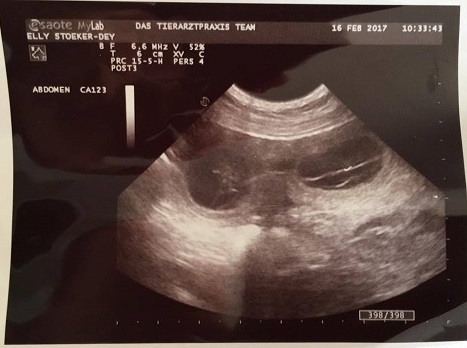

16.02.2017 Der "große" Tag war da und wir lüften Elenas süßes Geheimnis :-)

Früh morgens ging es mit Leon und Elena in Richtung Zülpich zu unserem Tierarzt Dr. Müller. 26 Tage nach der Hochzeit stand heute die Ultraschalluntersuchung an. Da alle Körperlichen- und Verhaltensveränderungen ziemlich sicher darauf hindeuteten das es geklappt hat, war ich mir sehr sicher heute ein erstes Foto von den F-chen zu erhalten. Ich sollte recht behalten :-)

"Wir sind schwanger" und dürfen uns jetzt sicher auf unsere "Antonellis" freuen die um den 24. März erwartet werden.

Es war einiges los in Elenas Bauch, es wird sicherlich kein kleiner Wurf, und wir sind sehr gespannt wie viele Fleckenzwerge es letztendlich werden.

Stellvertretend für alle F-chen stellen wir hier schon mal zwei vor ;-)